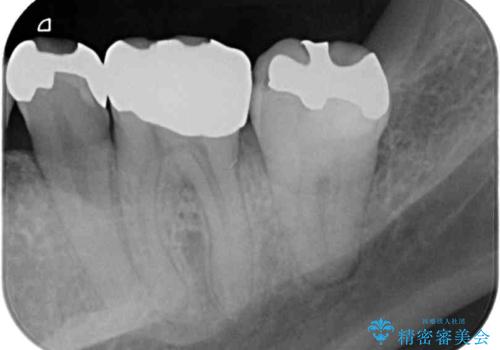

奥歯には目立つ銀歯が多くあるので、矯正治療後には下顎の銀歯をセラミッククラウンやセラミックインレーにより、補綴・修復治療することとしました。

上顎歯列全体を後方に移動させたため、口元の突出感も改善され、装置を外してからは口が閉じやすくなりました。

また、上下犬歯が接触するようになったため、奥歯にストレスのかからない歯ぎしりができるようになり、顎の疲れも改善されました。